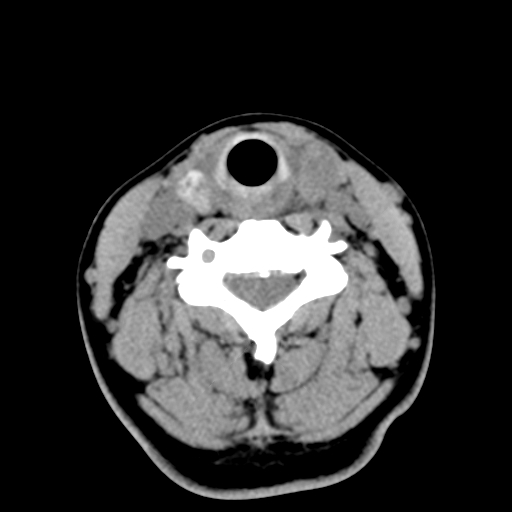

女,44岁,左颈部肿块伴疼痛两个月。患者不能做增强扫描。

左侧甲状腺明显肿大,密度不均匀性减低,正常之钙化基本消失,残留少许呈云雾状及颗粒状。其边缘不规则、不清晰,与前部联合处正常甲状腺不能分界不清,但尚可与周围其他组织分辨。颈动脉鞘区无明显淋巴结肿大。

多考虑:左侧甲状腺癌。

多考虑:左侧甲状腺占位,建议穿刺活检。